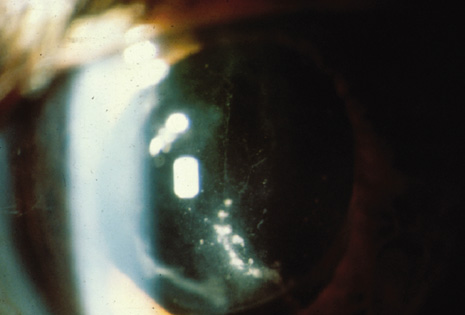

Endophthalmitis after intravitreal injection (Fig. 16) is an uncommon complication that has become the focus of attention in recent years as the use of intravitreal triamcinolone acetonide and various anti-angiogenesis medications have become available (Table 2). It is important to distinguish infectious endophthalmitis from a noninfectious pseudohypopyon caused by triamcinolone acetonide crystals (Fig. 17). Another modality, pneumatic retinopexy, is also rarely associated with the development of endophthalmitis. In the multicenter clinical trial on pneumatic retinopexy, one patient out of 103 eyes in the pneumatic retinopexy group developed endophthalmitis. A total of three endophthalmitis cases have now been reported following pneumatic retinopexy.115–117 The most common isolate is S. epidermidis and treatment approaches include standard intravitreal antibiotic injection as performed in postsurgical endophthalmitis. Strategies to reduce the risk of endophthalmitis include using a povidone-iodine ocular preparation (Fig. 18), using a lid speculum (Fig. 19), and avoiding needle contact with the lid margins and lashes (Fig. 20).

Fig. 16. Infectious endophthalmitis following intravitreal triamcinolone acetonide injection. Left: Marked conjunctival congestion, hypopyon, and prominent fibrin in the anterior chamber. Visual acuity is reduced to hand motion. Right: Higher-powered view of the anterior chamber shows marked fibrin strands in the anterior chamber.

Fig. 17. Noninfectious endophthalmitis after intravitreal triamcinolone acetonide A pseudohypopyon is created by the triamcinolone crystals in the anterior chamber. Notice the quiet conjunctiva, small, very white hypopyon, and minimal fibrin. This patient was examined on the second postinjection day as part of a routine follow-up protocol. No treatment was given and the psuedohypopyon cleared spontaneously.

Fig. 18. A povidone-iodine preparation is used to prepare the eye for an intravitreal injection.

Fig. 19. A lid speculum maintains the lid position and allows access to the pars plana region for intravitreal injection.

Fig. 20. In spite of the preparation with povidone-iodine, it is recommended that needle contact with the lid margins and lashes be avoided.